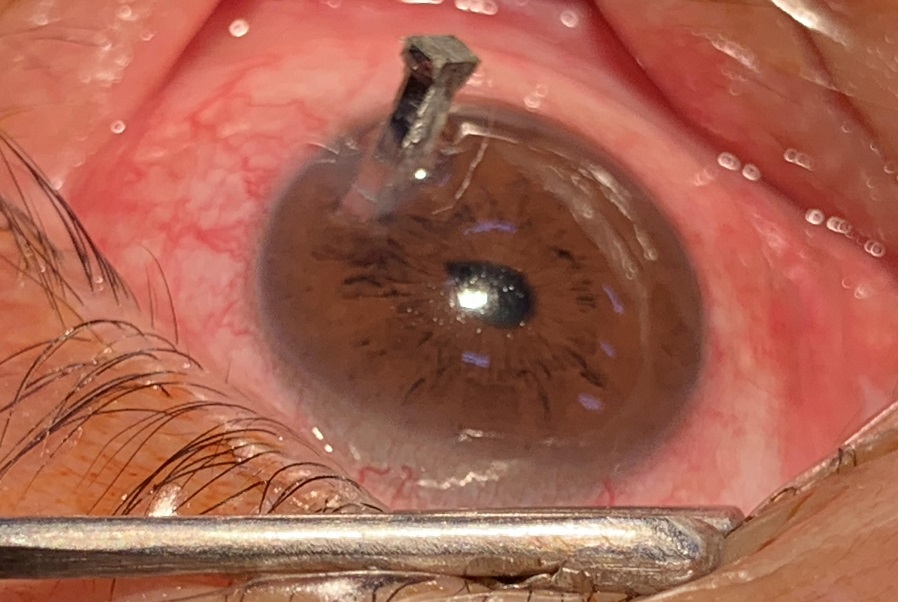

TS.BS Trần Khánh Sâm, Bệnh viện Mắt Trung ương, người phụ trách kíp trực cấp cứu bệnh nhân, cho biết, qua thăm khám và quan sát trên kính hiển vi, bác sĩ xác định bệnh nhân bị cây đinh xuyên thấu giác mạc, mống mắt, thủy tinh thể và gây vỡ thủy tinh thể, xuyên củng mạc sau.

Hình ảnh chiếc đinh dài 3cm cắm sâu vào mắt bệnh nhân